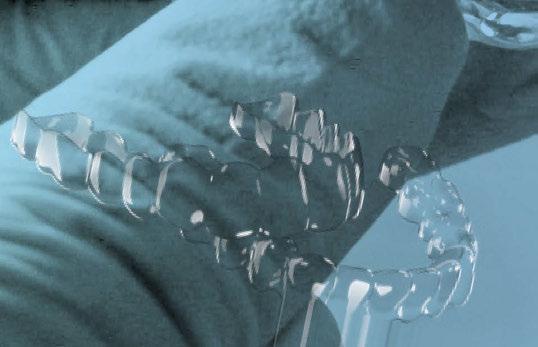

A continuación, para la planificación de los implantes dentales y el diseño de la férula de cirugía guiada se usó la plataforma digital RealGUIDE®. Para ello se realizó el matching, por un lado, del archivo STL del encerado digital; y, por otro, del archivo 3D. De esta manera, se pudo analizar el tejido óseo residual apical a cada diente y la posición de la raíz respecto a las corticales vestibular y palatina. También se estudió la relación de los contornos óseos con los tejidos blandos y con la posición final de los márgenes cervicales de la restauración protésica, pudiendo así planificar la posición 3D correcta de los implantes. En esta primera fase se diseñó una férula quirúrgica para la elevación de seno bilateral a partir del software RealGUIDE™, que nos sirvió de guía para el diseño de las ventanas de acceso. Esta férula se imprimió con la impresora 3D Formlabs® (Figura 7)

A los 6 meses de cicatrización, se realizó un nuevo CBCT, obteniendo un nuevo archivo DICOM que alineamos con el STL del encerado. De esta manera, se planificó la posición de los implantes a 4 mm del margen de la restauración final y se diseñó y confeccionó la férula de cirugía guiada dentosoportada en 12-13 y 22-23, la cual imprimimos con la impresora 3D Formlabs®. El provisional

de carga inmediata lo diseñamos con el programa de diseño 3D Exocad® a partir del encerado y se imprimió también en clínica con la misma impresora 3D (Figuras 14-16).